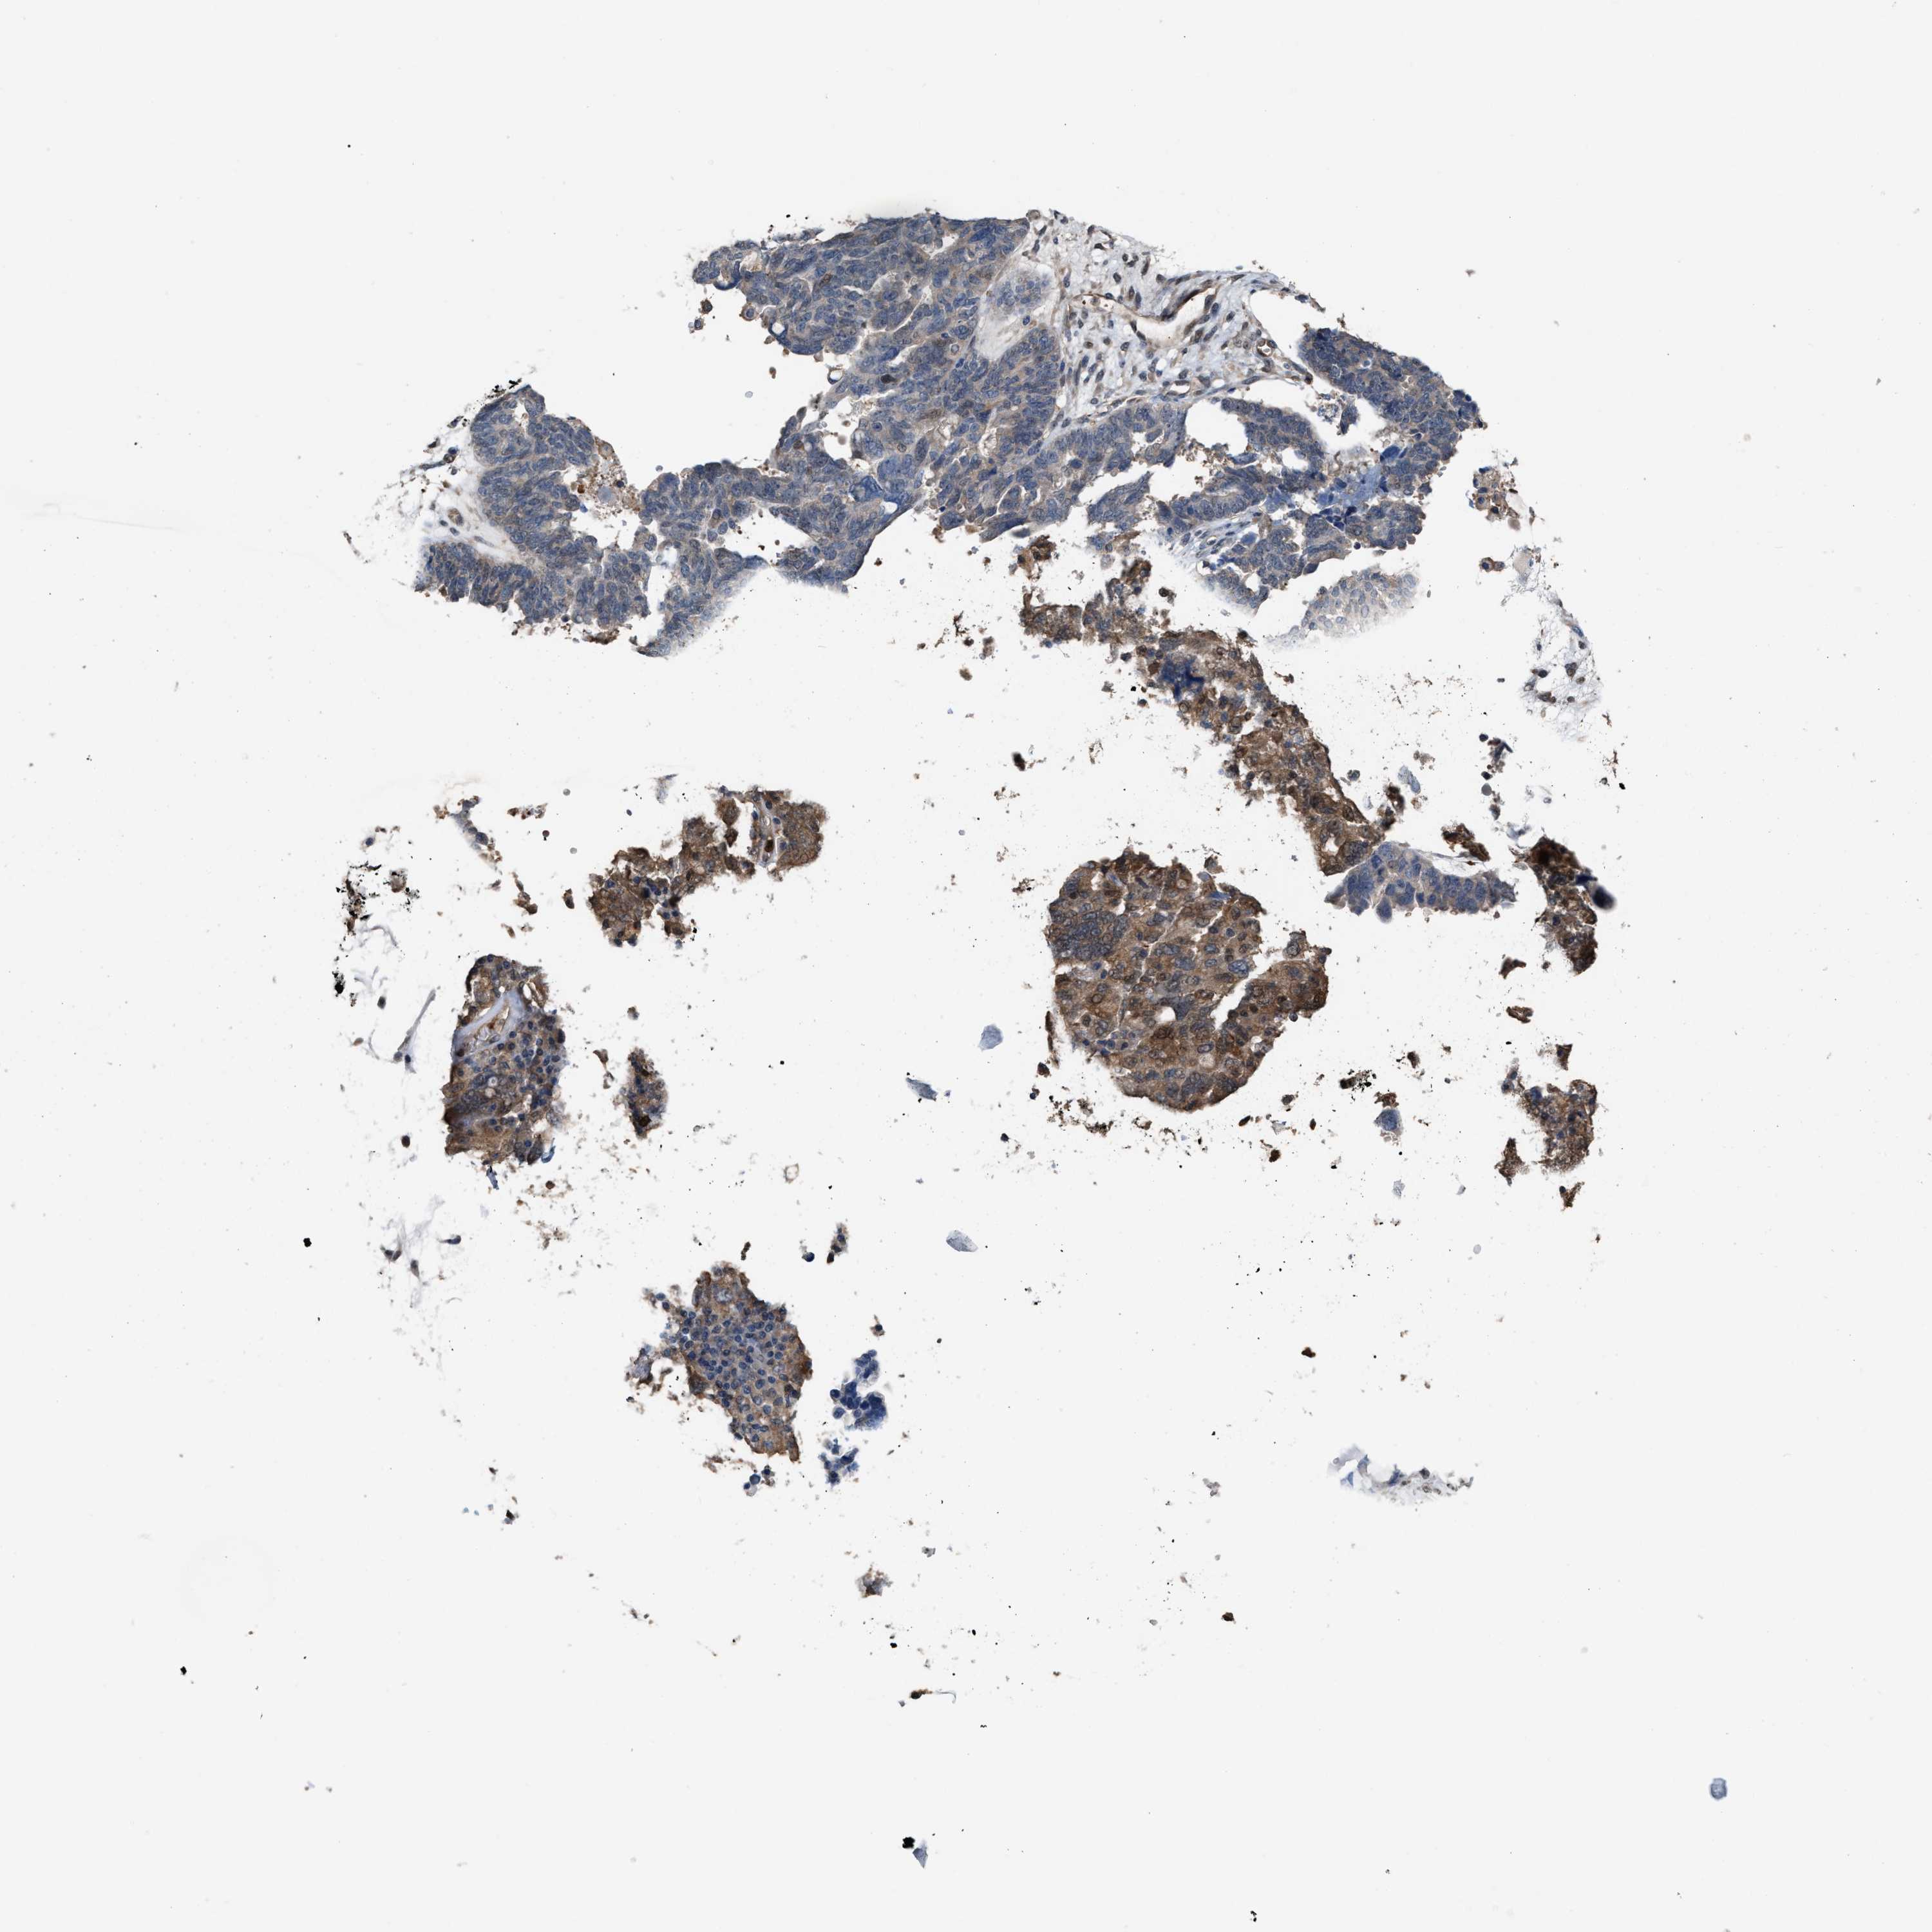

OVARIAN CANCER - Protein expressioni

A mouse-over function shows sample information and annotation data. Click on an image to view it in a full screen mode. Samples can be filtered based on level of antibody staining by selecting one or several of the following categories: high, medium, low and not detected. The assay and annotation is described here.

Note that samples used for immunohistochemistry by the Human Protein Atlas do not correspond to samples in the TCGA dataset.

Antibody stainingi

Antibody staining in the annotated cell types in the current human tissue is reported as not detected, low, medium, or high, based on conventional immunohistochemistry profiling in selected tissues. This score is based on the combination of the staining intensity and fraction of stained cells.

Each image is clickable and will lead to virtual microscopy that enables deeper exploration of all samples and also displays staining intensity scores, fraction scores and subcellular localization as well as patient and tissue information for each sample.

Antibody HPA019735

Staining

High

Medium

Low

Not detected

Intensity

Strong

Moderate

Weak

Negative

Quantity

>75%

75%-25%

<25%

None

Location

Nuclear

Cytoplasmic/membranous

Cytoplasmic/membranous,nuclear

Cystadenocarcinoma, serous, NOS

Carcinoma, endometroid

Cystadenocarcinoma, mucinous, NOS

Carcinoma, NOS